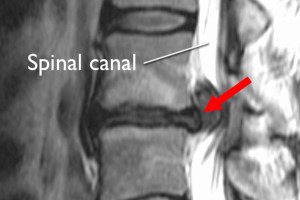

脊柱管狭窄

脊柱管的变窄,可能会对脊髓或神经施加压力,引起疼痛和不适。